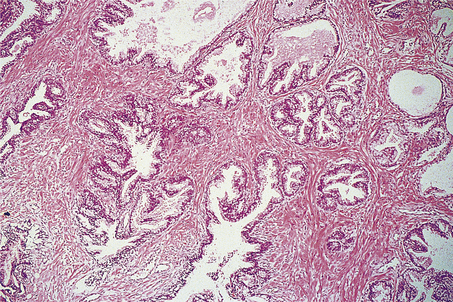

Appearances

At presentation most bladder tumours are low-grade and papillary, with fronds lined by a slightly thickened urothelium showing little cytological abnormality (Fig. 20.4). Usually there is no invasion of the lamina propria. Papillary tumours are frequently multiple, consistent with a widespread field change throughout the urothelium including the upper tract, even though it is histologically normal.

image

Fig. 20.4 Transitional cell carcinoma of the bladder. These common tumours usually project into the bladder lumen before invading the underlying bladder wall.

In contrast, about 20% of tumours are solid and invasive at presentation extending into the detrusor muscle, and if beyond they render the tumour fixed clinically. These tumours are high grade with marked cytological abnormalities; aberrant squamous or adenocarcinoma differentiation may be seen, and there are other histological variants too. The background urothelium often shows carcinoma in situ, which is considered to be the precursor lesion, and may give rise to further high-grade invasive tumours.

Between these two extremes of tumour type there are some high-grade papillary tumours; these may have background carcinoma in situ, and are more likely to progress to invasive carcinoma.